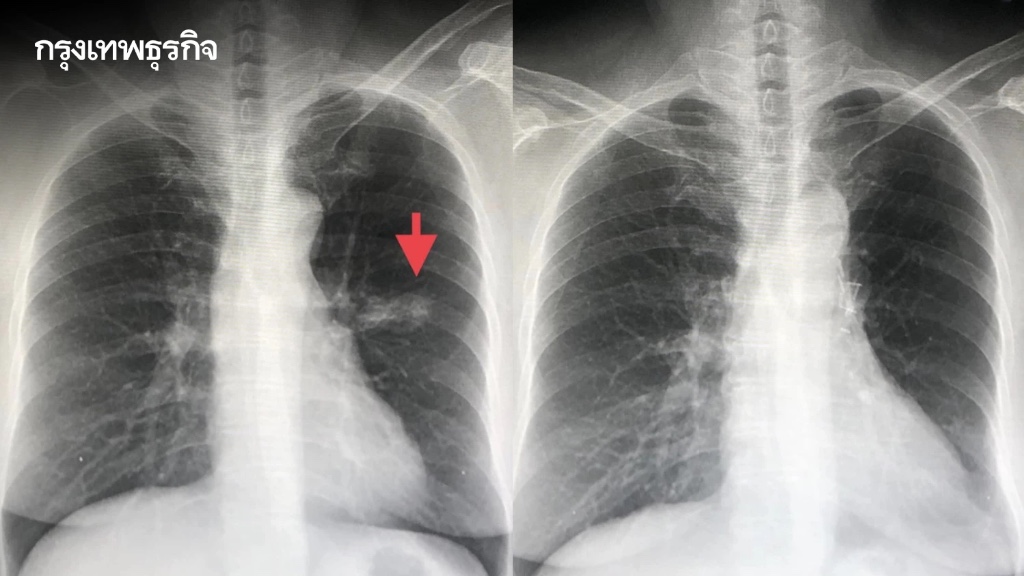

ภาพจาก : กรุงเทพธุรกิจ

ดังนั้น มะเร็งยังเป็นภัยเงียบอันดับ 1 และมะเร็งปอดคือมะเร็งที่อันตรายที่สุดในตอนนี้ แต่หลายปัจจัย “ป้องกันได้” จากพฤติกรรม ไม่ว่าจะเป็นการเลิกบุหรี่ เลี่ยงฝุ่น และการตรวจสุขภาพที่อาจช่วยลดความเสี่ยงได้มากกว่าที่คิดครับ